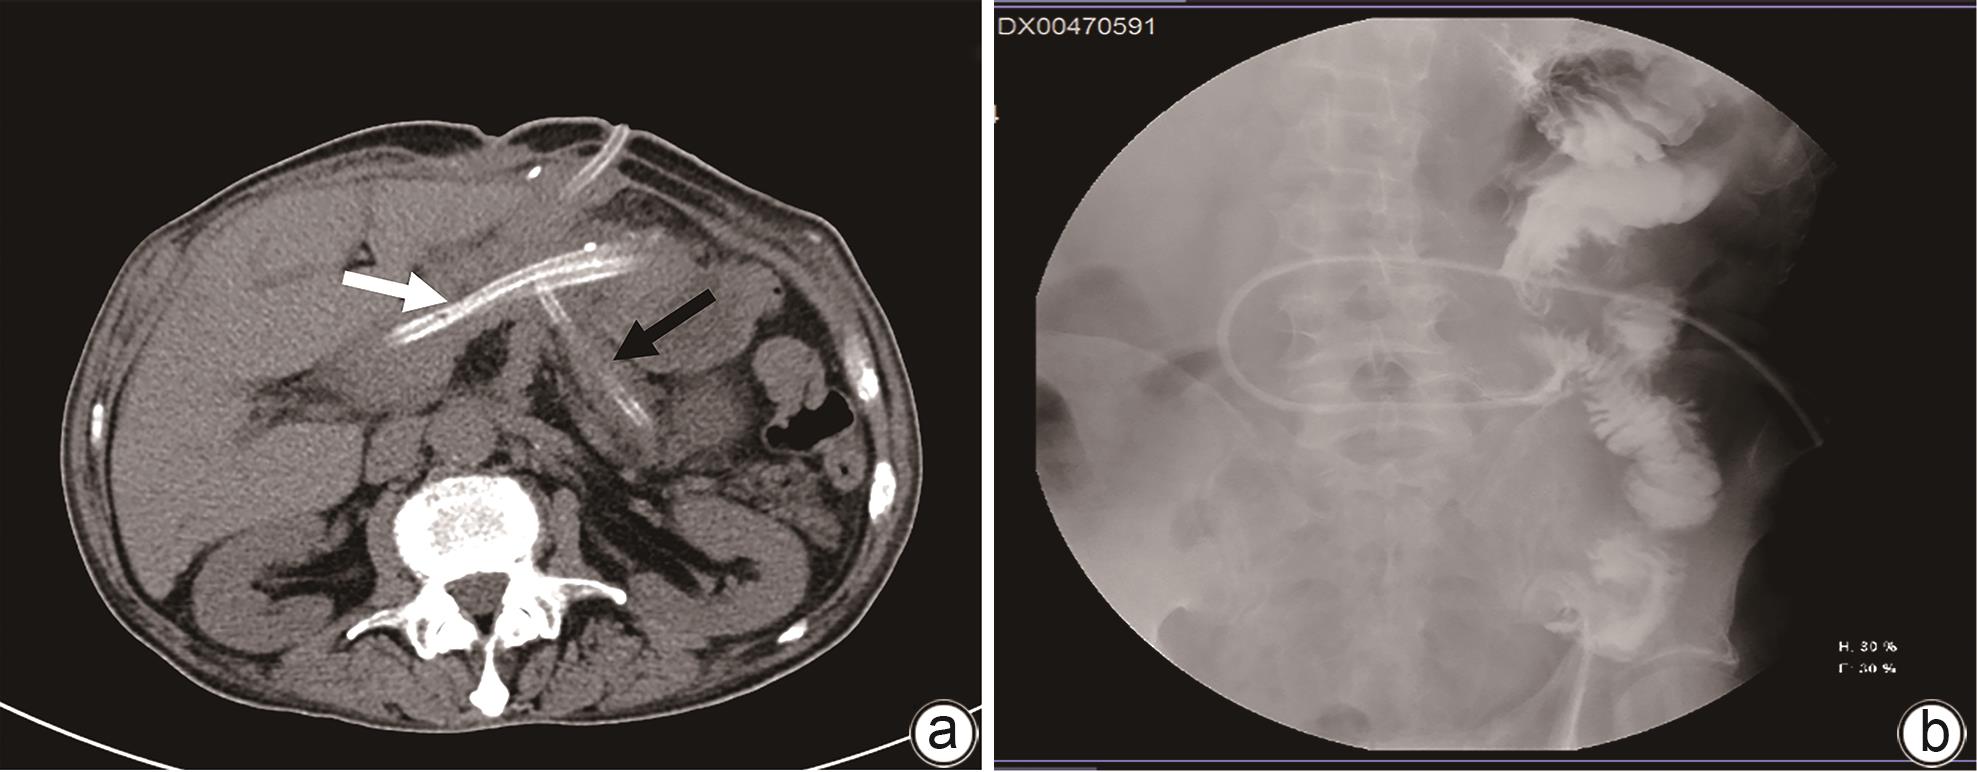

摘要: 目前,对于胰十二指肠切除术后胰瘘伴出血的治疗,血管介入和手术是主要的治疗手段,但以上治疗方法都存在一定的弊端,例如手术后出现再次胰瘘、出血、腹腔感染等并发症,介入治疗难以发现出血部位等。本文报道1例经引流管窦道置入Foley导尿管球囊压迫治疗胰十二指肠切除术后复杂性胰瘘伴静脉大出血患者。经导尿管球囊加压止血及有效引流,患者出血停止,消化道瘘痊愈,无胰腺假性囊肿、肠缺血、门静脉高压等并发症。Abstract: At present, vascular intervention and surgery are the main methods for the treatment of pancreatic fistula with bleeding after pancreaticoduodenectomy, but these treatment methods have certain drawbacks, such as the complications of pancreatic fistula, bleeding, and abdominal infection after surgical treatment, and interventional treatment sometimes fails to identify the bleeding site. This article reports a case of complex pancreatic fistula with massive venous hemorrhage after pancreaticoduodenectomy treated with Foley catheter balloon compression through the drainage tube sinus. Bleeding was arrested and gastrointestinal fistula was cured after catheter balloon compression and effective drainage, with no complications such as pancreatic pseudocyst, intestinal ischemia, and portal hypertension.